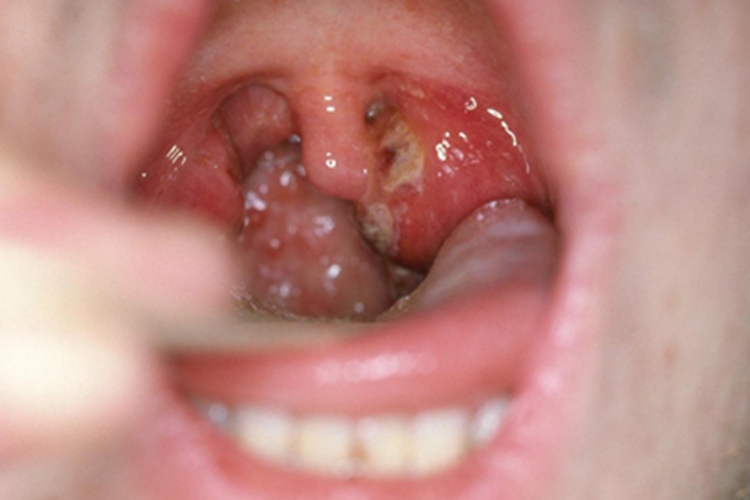

急性咽炎起病较急,先有咽部干燥、灼热,继有明显咽痛,吞咽时尤重,有时可伴有发热、头痛、食欲减退和四肢酸痛等。检查可见咽喉红肿,黏膜呈急性弥漫性充血,咽后壁淋巴滤泡隆起,表面可见黄白色渗出物。